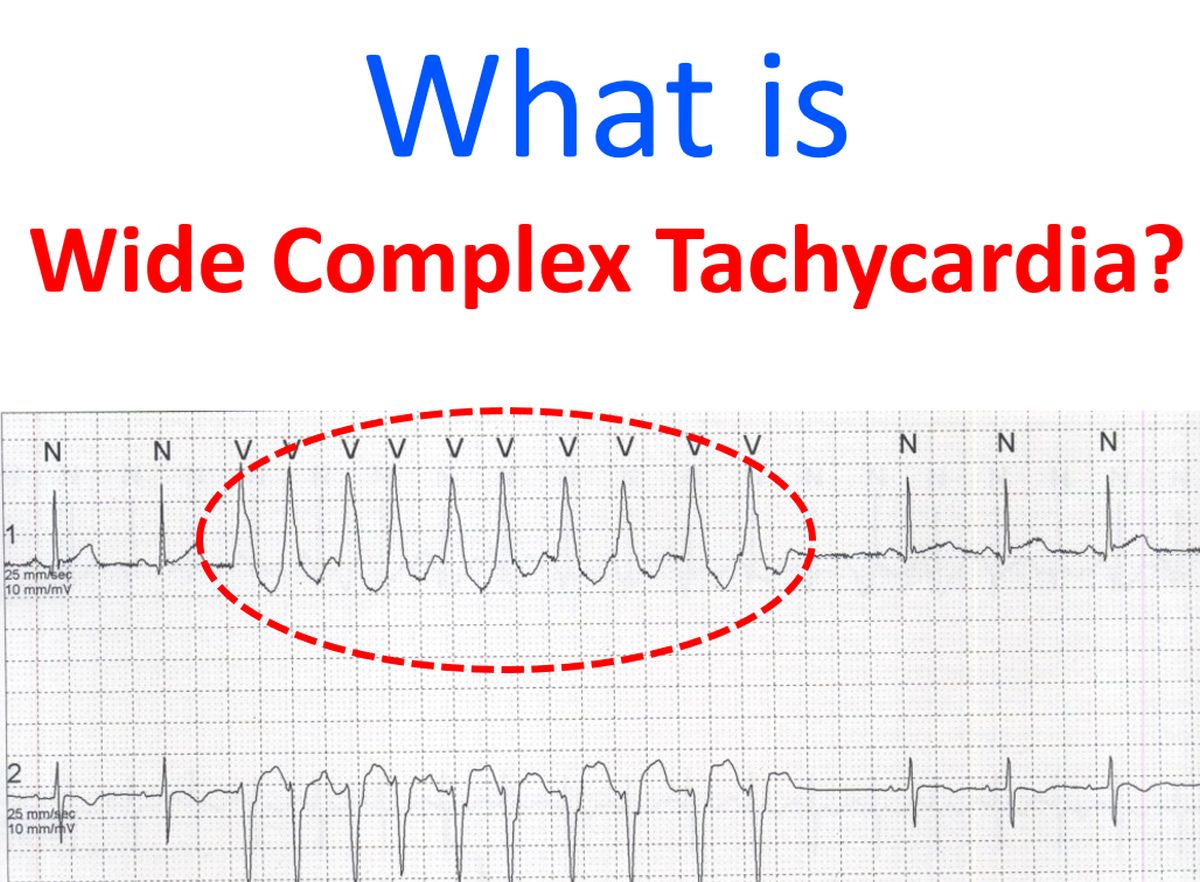

QRS Interval On Your Watch ECG Narrow Normal And Wide 57 OFF

QRS Interval On Your Watch ECG Narrow Normal And Wide 57 OFF

https://johnsonfrancis.org/general/wp-content/uploads/2008/08/What-is-Wide-Complex-Tachycardia.jpg